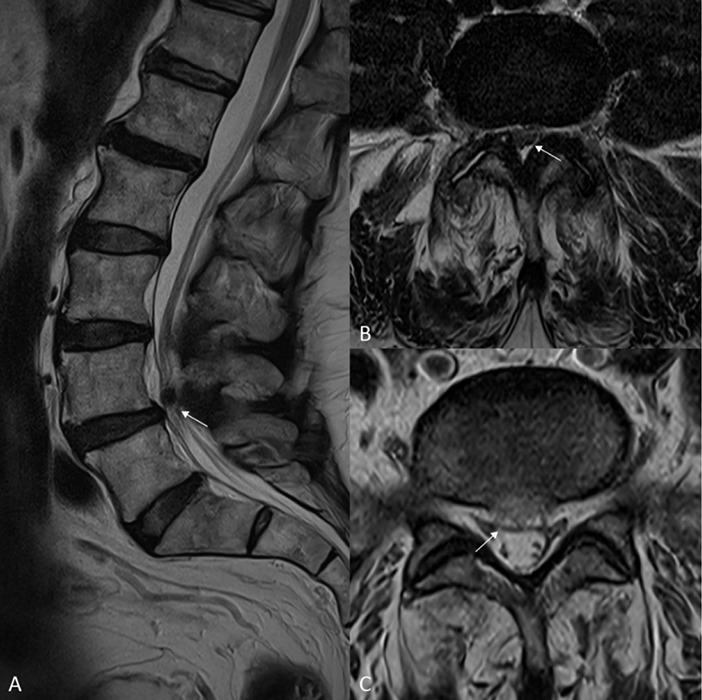

Teaching point: Denervation pseudohypertrophy of the medial gastrocnemius muscle is an uncommon cause of calf swelling that may be secondary to chronic radiculopathy.